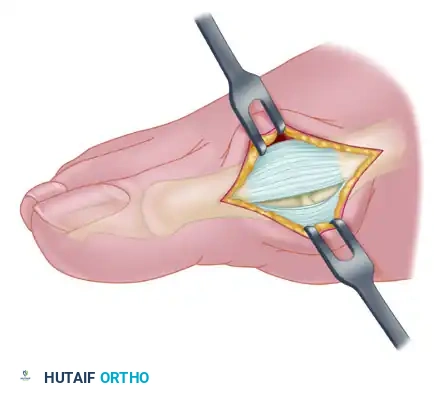

5. The Lateral Release

The lateral release is the most technically demanding portion of the modified McBride procedure. It can be performed transarticularly (through the MTP joint) or via a separate dorsal incision in the first web space.

Steps of the Lateral Release:

1. Release of the Suspensory Ligament: The lateral sesamoid suspensory ligament is incised, allowing the sesamoid apparatus to mobilize medially.

2. Release of the Deep Transverse Metatarsal Ligament: This ligament, connecting the first and second metatarsal heads, is sharply divided. Care must be taken to protect the underlying neurovascular bundle.

3. Adductor Hallucis Tenotomy: The conjoined tendon of the adductor hallucis is identified at its insertion on the base of the proximal phalanx and the lateral sesamoid. It is sharply detached.

4. Lateral Capsulotomy: If the joint remains tight, a vertical lateral capsulotomy is performed.

Following the lateral release, the surgeon should be able to manually reduce the hallux into a neutral or slightly varus position without resistance. The sesamoids should reduce anatomically beneath the metatarsal head.